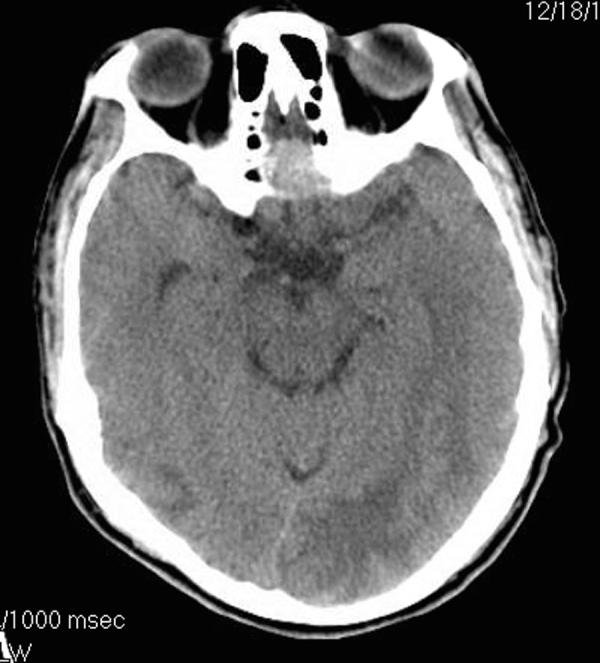

The Mycobacterium avium-intracellulare complex (MAC) is an uncommon cause of brain abscesses even in patients with acquired immunodeficiency syndrome (AIDS). We present a case of a multiple MAC brain abscesses, confirmed by brain biopsy and culture, in a patient with AIDS. The patient's initial symptoms were weakness, confusion and headaches. The patient was initially treated for toxoplasmosis and pyogenic bacterial brain abscesses with no resolution. Following treatment for MAC the patient's abscesses resolved.

鸟分枝杆菌-胞内分枝杆菌复合体(MAC)即使在获得性免疫缺陷综合征(AIDS)患者中,也是脑脓肿的不常见病因。我们报告一例经脑活检和培养确诊为多发性MAC脑脓肿的AIDS患者。患者最初的症状是虚弱、意识模糊和头痛。患者最初接受了弓形虫病和化脓性细菌性脑脓肿的治疗,但病情未缓解。针对MAC进行治疗后,患者的脓肿消退。